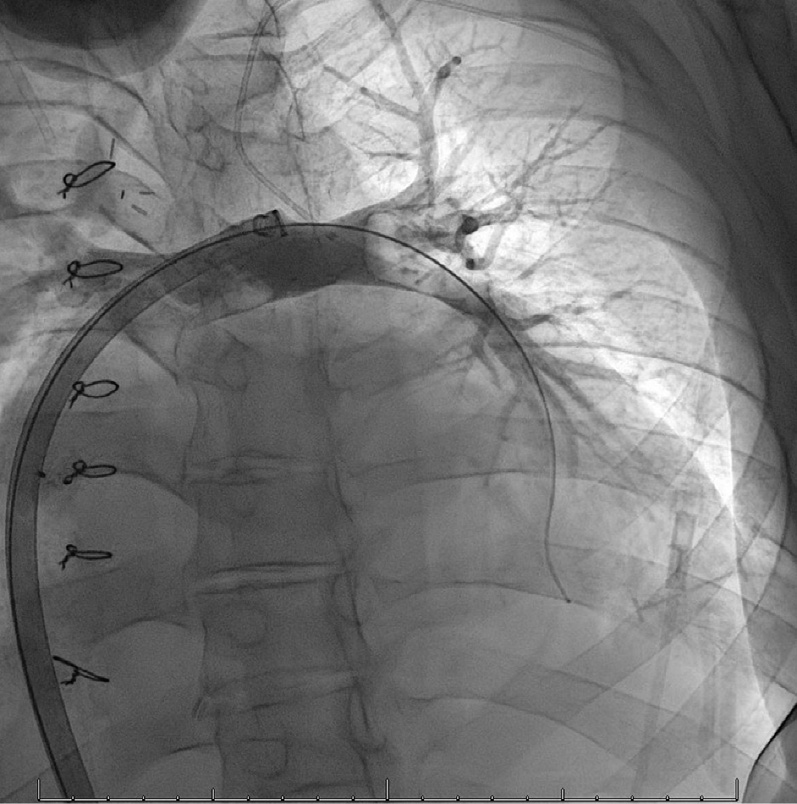

,故开始利尿治疗。在多日利尿治疗后,低氧血症仍未见改善,患者接受了右心导管检查(RHC)和Fontan血管造影

。RHC显示右侧充盈压升高。血管造影显示左肺动脉远端有较大血栓(图2)。

图2 右心导管检查显示:左肺动脉栓塞

经过一系列排查,明确诊断为肺栓塞后,经多学科团队商定行血栓抽吸术。取栓术后血管造影检查显示血栓成功清除。术后肺动脉压力未立即下降,这可能与术中容量负荷和造影剂输注引起的短暂性压力升高有关,但血氧饱和度很快恢复并稳定在85%-90%的基线水平。至此,宣告这场战役取得阶段性胜利。